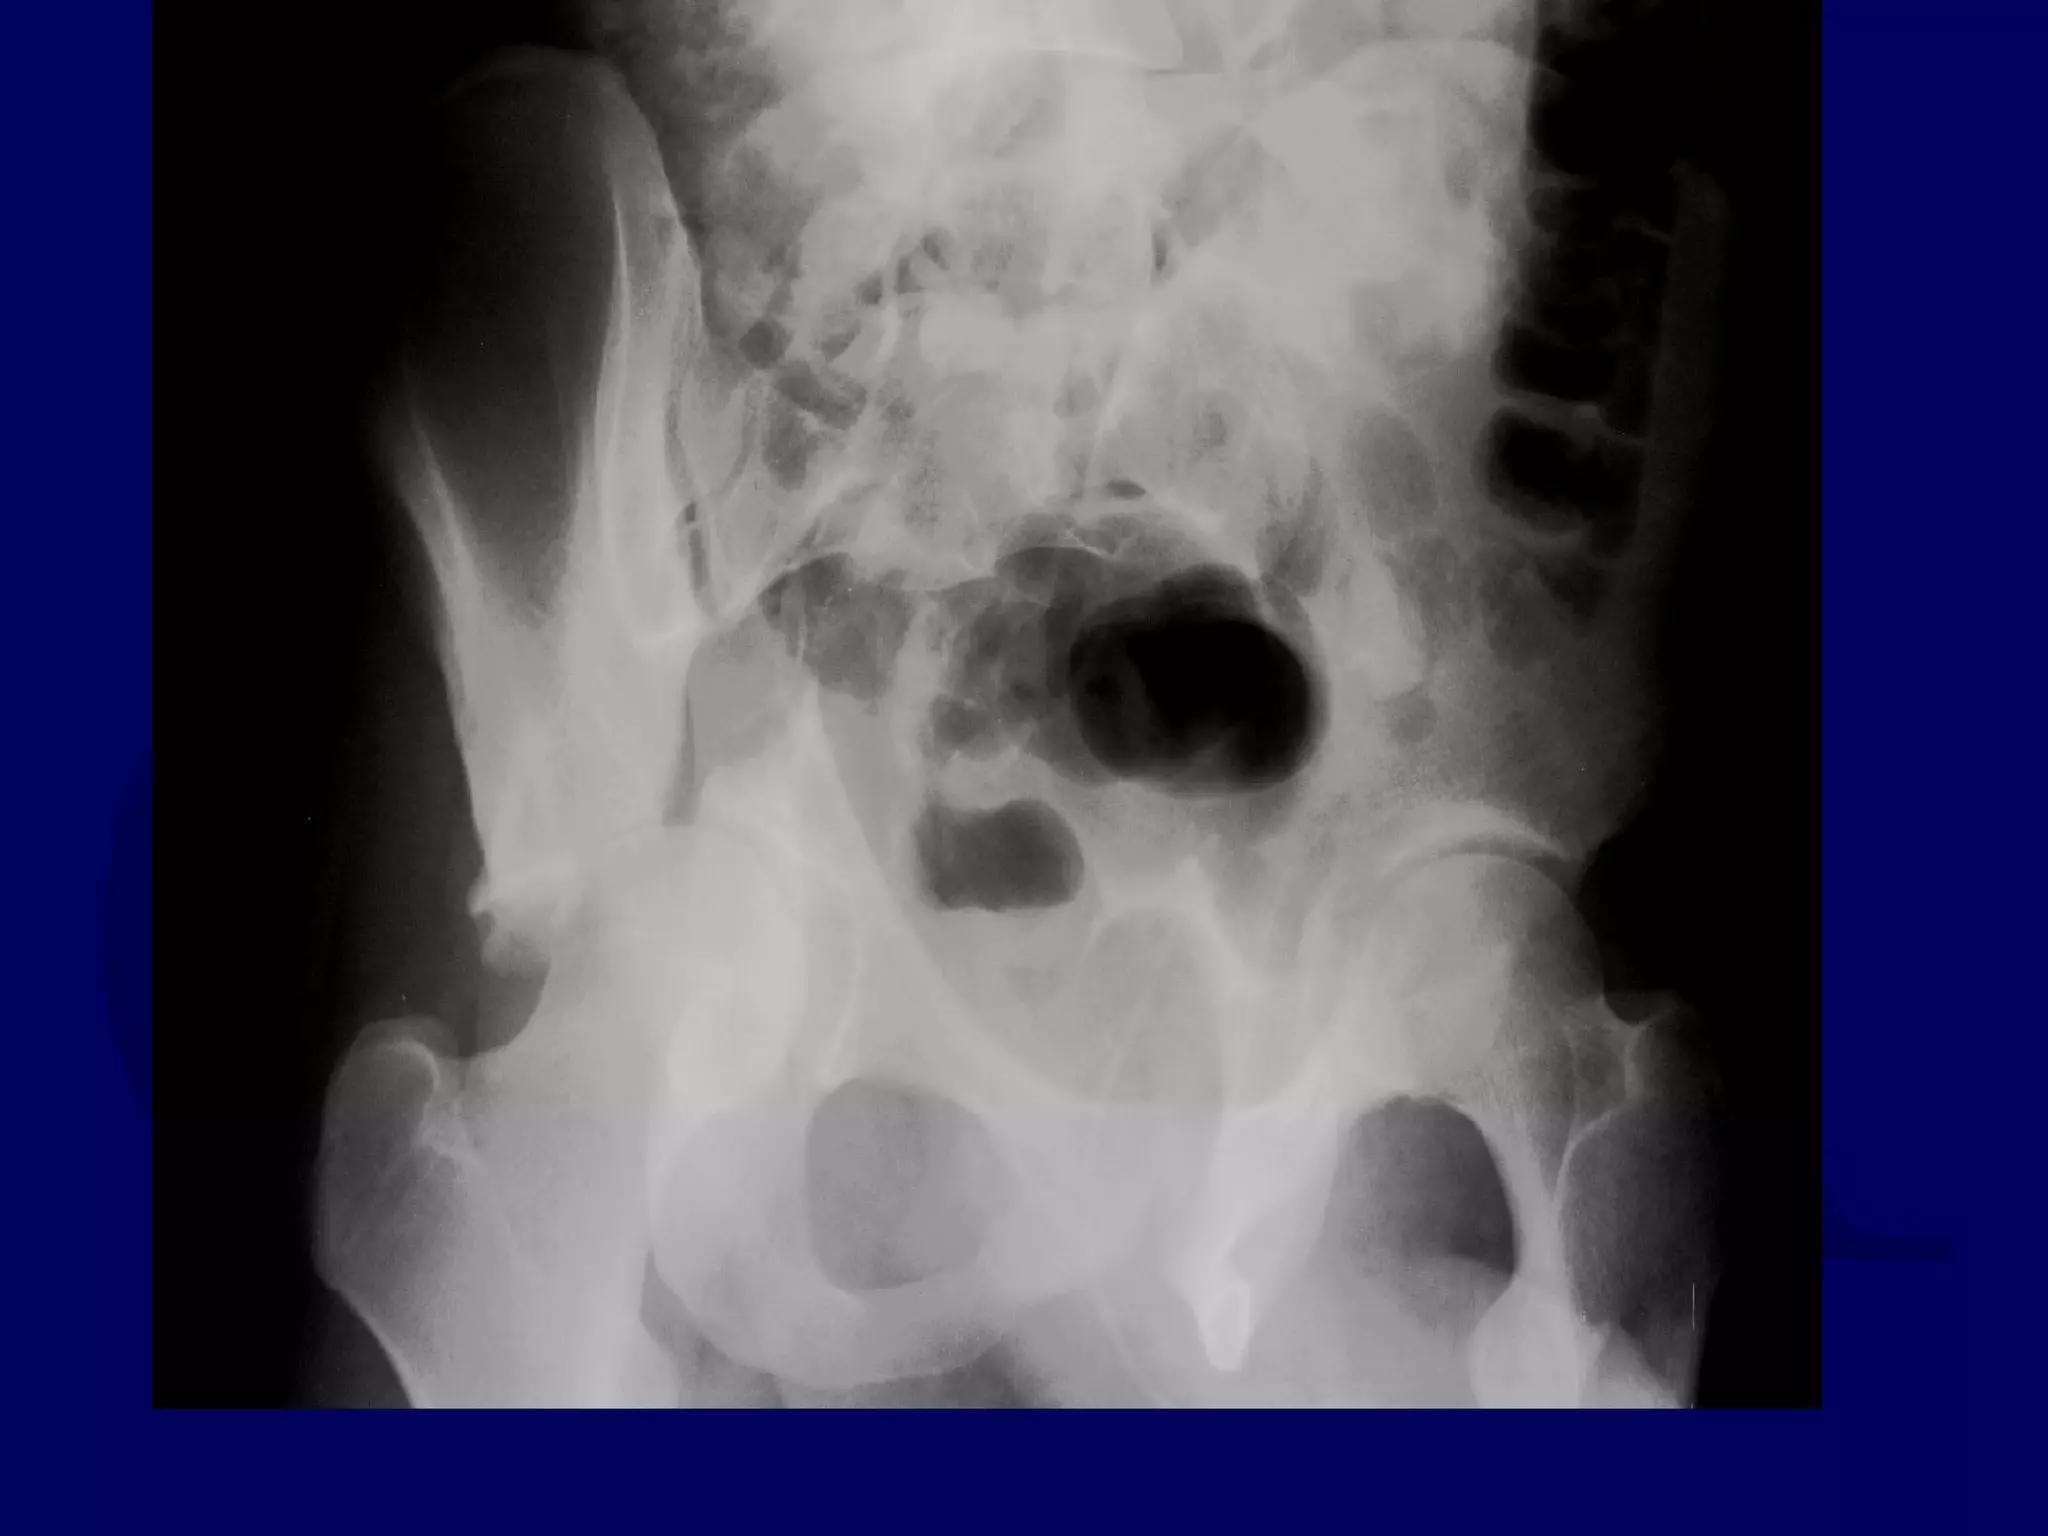

R.H. 98.11.22

R.M. 99.02.17